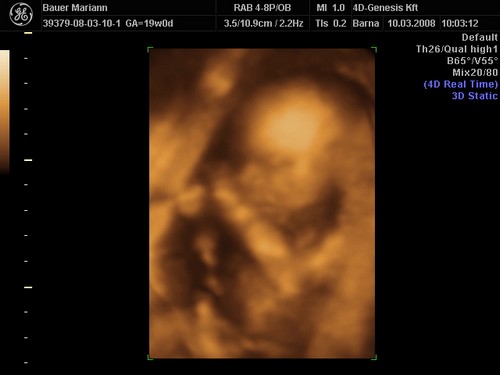

lányok tegnap bevettem egy maltofer vasat és olyan hasmenésem volt most reggel hogy hajjaj ez normális :?: na meg két pici tűszúrásnyi piros pötty lett a pocakomon,jujj megyek mert 10re oda kelll érni a genesisbe látjuk a kicsiket :D jajjj de jó

KépetKépetKépet

Drága picikéim nem voltak túl szereplős hangulatukba úgy kellett kikönyörögni őket a méhlepényből,és még igy sem letek túl élesek a képek.jázmin 266gr ,amy 300gr,jázmin egyszer úgy fejberúgta amyt úgy sajnáltam :D olyan édes formás kiscsajok el vagyok ájulva ,szép egézségesek tele pocakkal,megzabálom őket :D

De nekem eltalálták a 4DGenesisben, nálam tényleg 2 kukis van, igaz, én 2 héttel idősebb terhes voltam, mint te az első 4D-s kukucson.